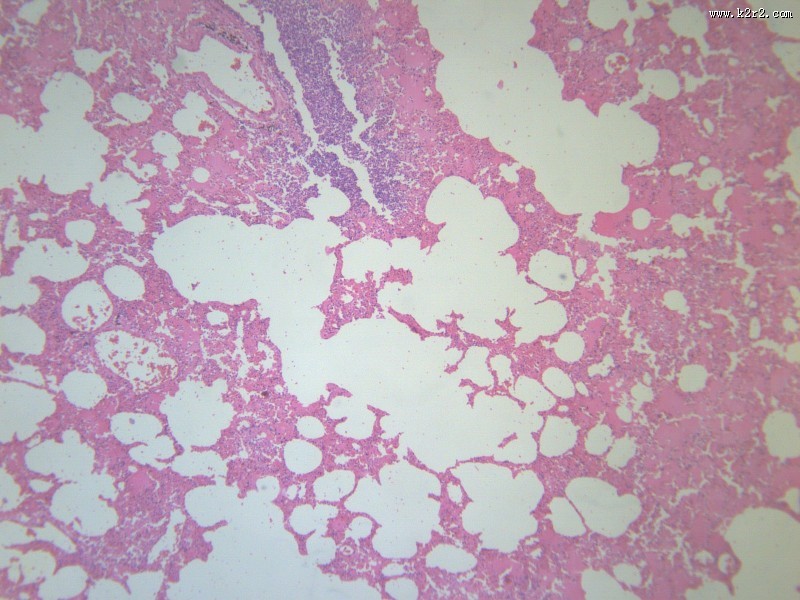

小叶性肺炎 - 第1张

小叶性肺炎

医学

显微切片

炎症

肺炎

bronchopneumonia

支气管肺炎